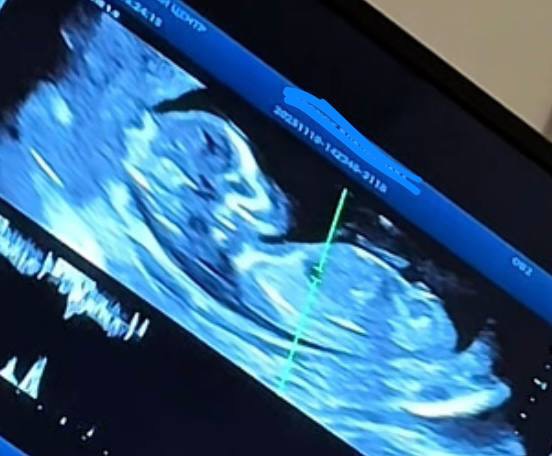

Добрый вечер девочки, была на первом скрининге в ПЦ🥰

Врач сразу сказал пол, и он верный 💙

По Анатомии все в норме, удивил меня один момент, я ходила и думала что срок у меня 13 недель, узист сказал что соответствует 14 неделям 😱